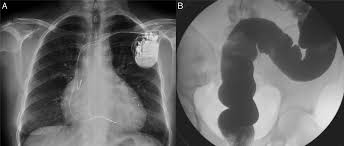

Rev Soc Bras Med Trop. 22 de abril de 2020. Las etapas avanzadas de la enfermedad cardíaca de Chagas y la edad tienen una asociación significativa con la presencia de RAMs. Además, se identificó la tos como el principal evento adverso observado con frecuencia de los inhibidores de la ECA.